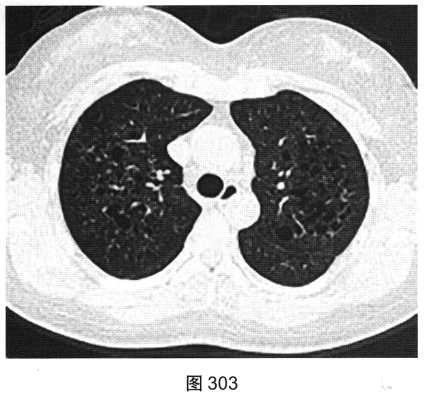

- [材料题] 患者女性,32岁,因“间断刺激性干咳1年,发现肺部囊性病变8个月”就诊。患者无发热、咯血、胸痛、呼吸困难。服甘草片、阿莫西林无明显好转。胸部HRCT如图302~图307所示。

- 多项选择题1.患者胸部HRCT的阳性征象有( )

- 多项选择题2.影像检查所示肺内主要病变的形态、分布特点为( )

A、囊状透亮影形状不规则、大小不一

C、囊状透亮影形状规则,大小及肺内分布均匀

G、囊壁较薄、略欠均匀,部分囊壁欠连续